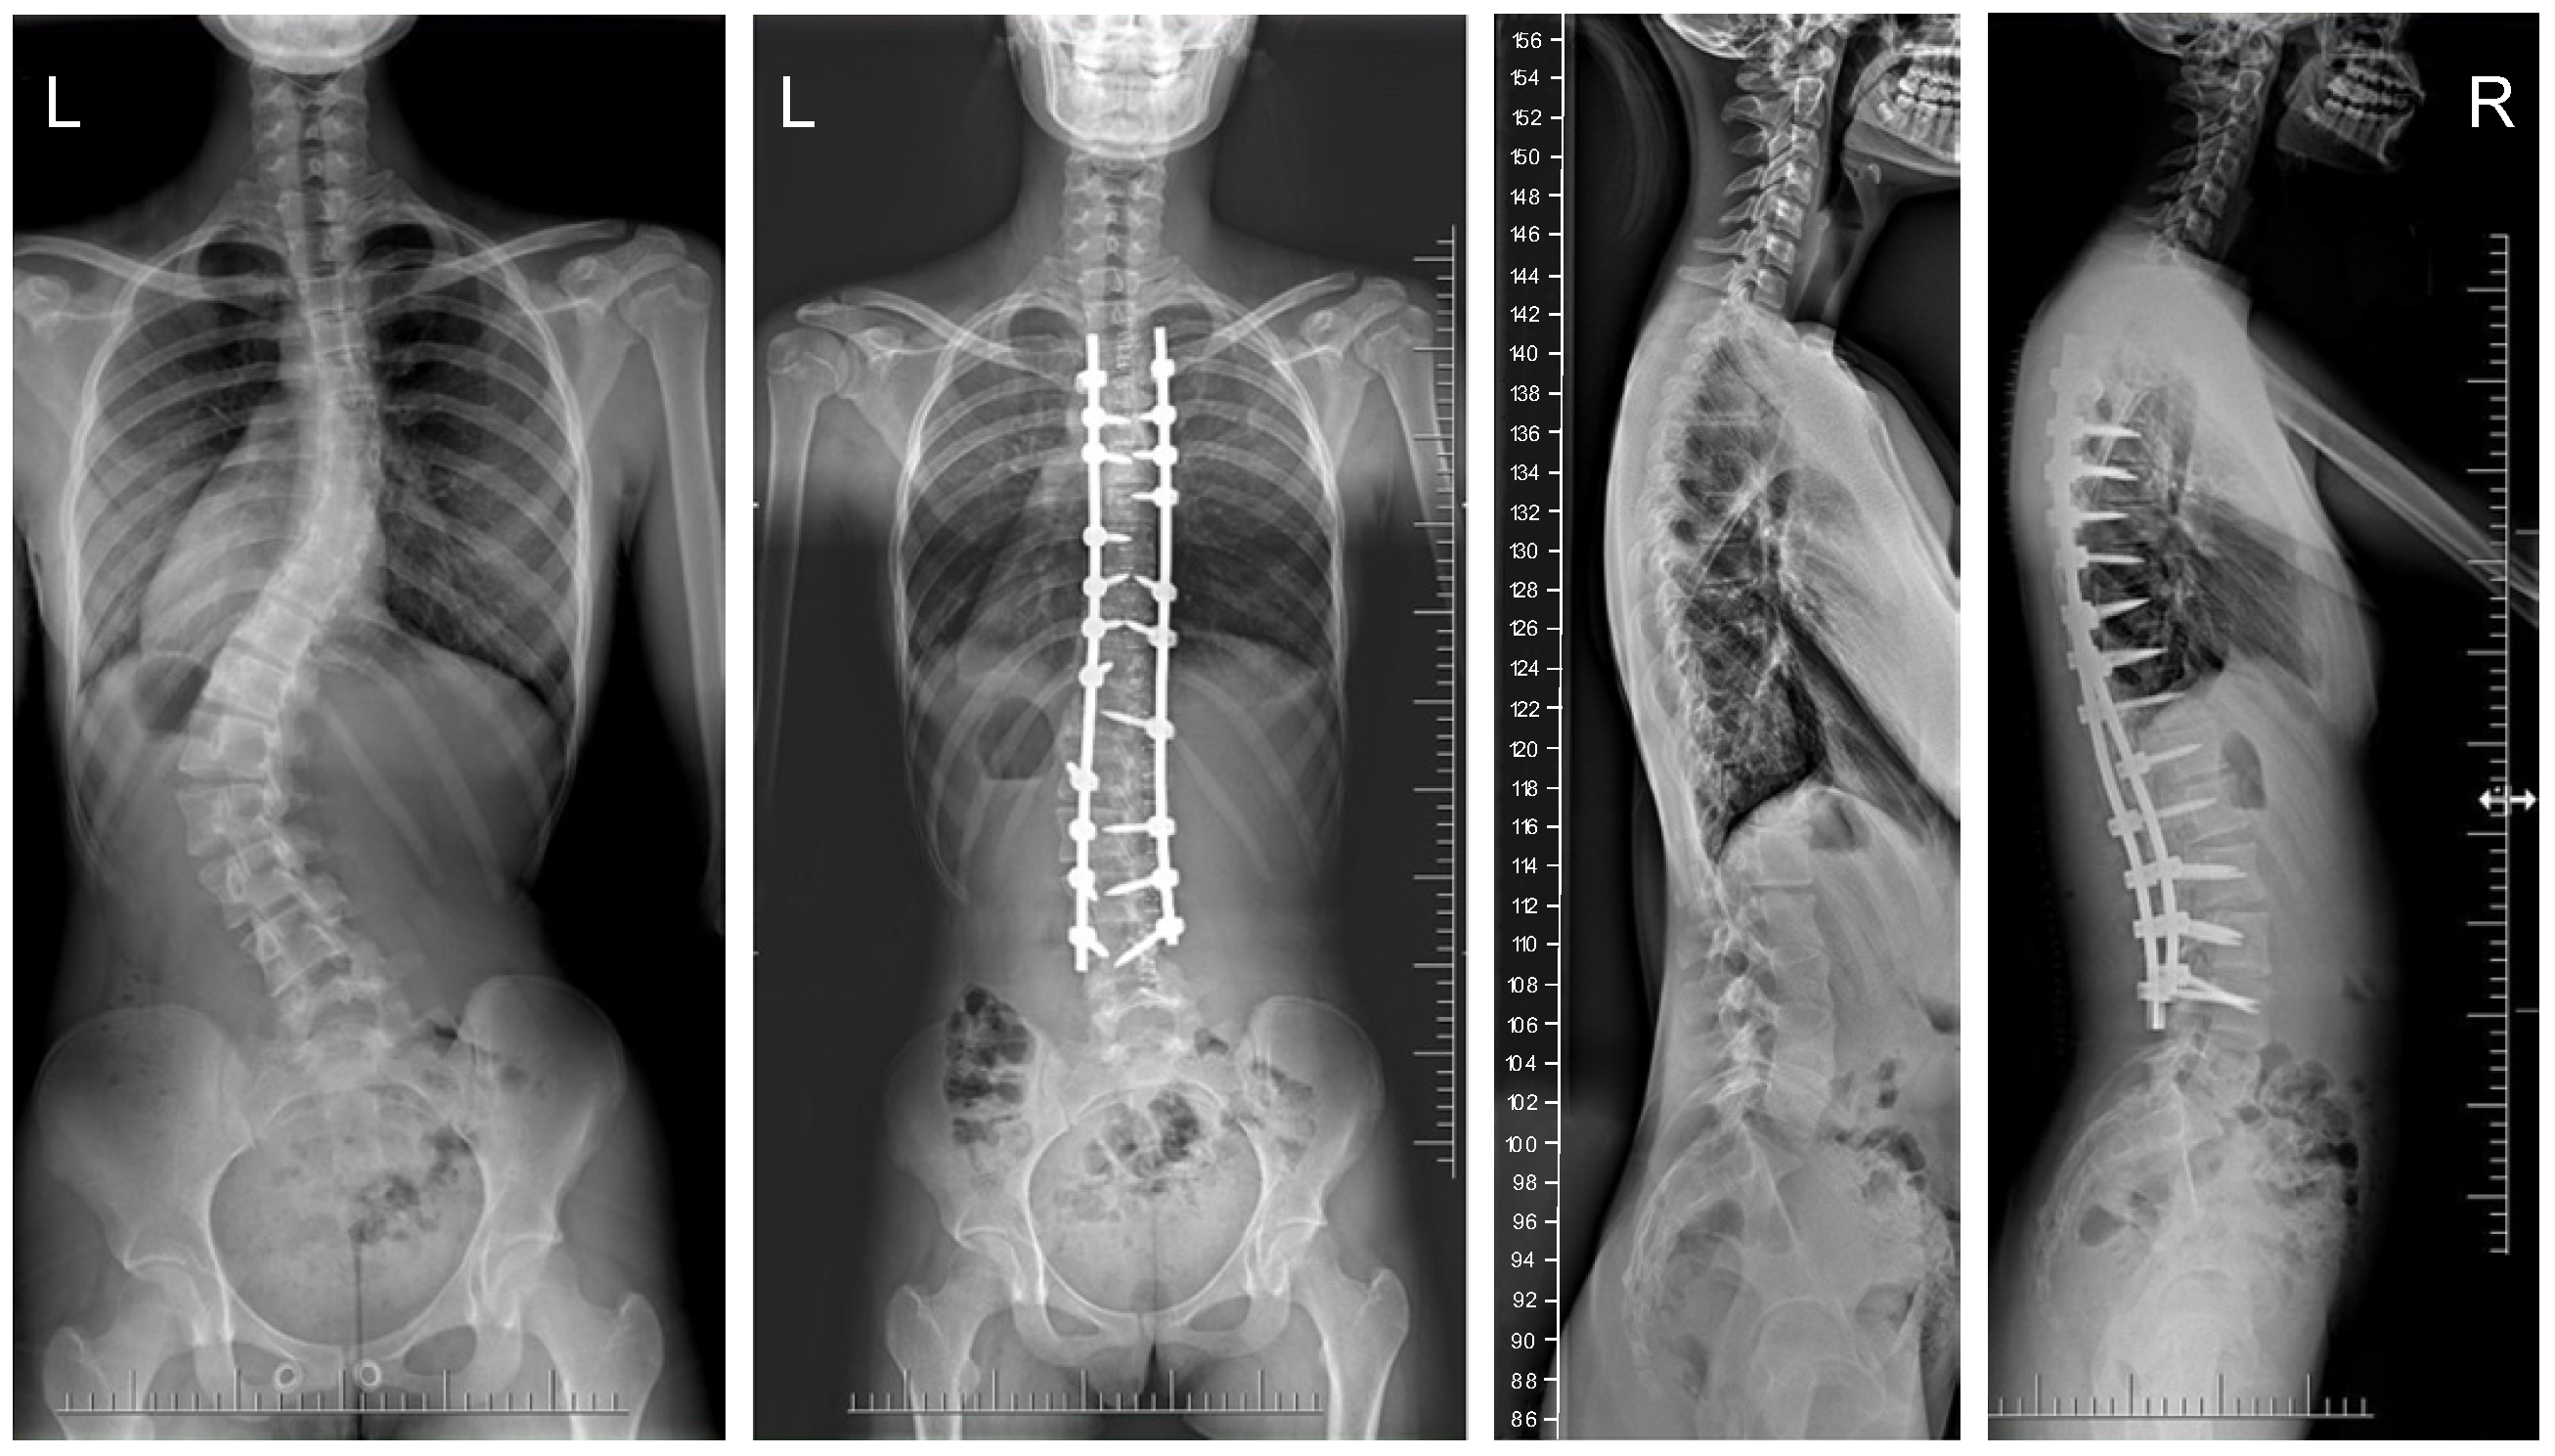

Figure 3.

X-rays of a 15-year-old girl with AIS, treated with larger screw sizes of 6.0 and 6.5 mm and 2 cobalt–chromium rods of 6.0 mm (G2). X-rays show curve before surgery and correction after surgical treatment.